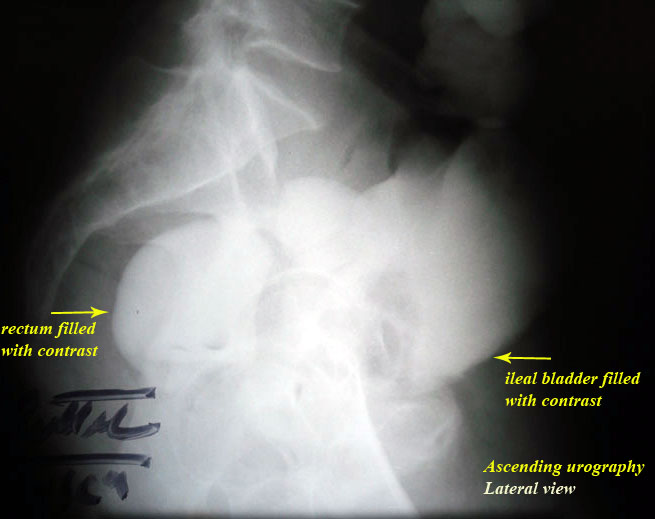

treatment. By difficulty we persuaded him to do ascending urography

" see photos".

Do you think that these photos were

convincing for the patient?